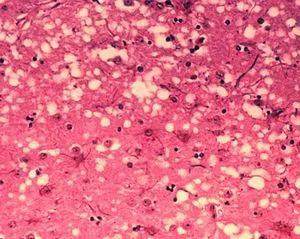

被朊毒体感染的脑组织产生了海绵状空洞 图片来源:wikipedia